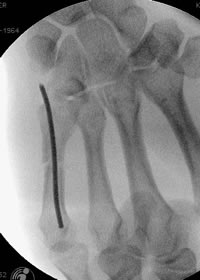

läßt sich leicht mit der retrograden Nagelung verwirklichen. Dabei wird an der Basis des MHK mit dem Pfriem der Markraum eröffnet. Danach weirden ein oder zwei 1.8 mm oder 2 mm starke Kirschnerdrähte eingebracht. Die Drähte werden mit dem stumpfen Ende, das leicht gebogen wird, eingeschoben. Die scharfe Spitze wird abgekniffen und der Draht in ein Jacobsfutter eingespannt. Mit der gebogenen Spitze läßt sich die Fraktur durch Drehen des Drahtes reponieren.

Anterograde Nagelung der Köpfchenfraktur am Mittelhandknochen.

Selbst eine basisnahe Fraktur läßt sich sofort und übungsstabil versorgen. Die Operation wird ambulant in iV-Lokalanästesie durchgeführt.